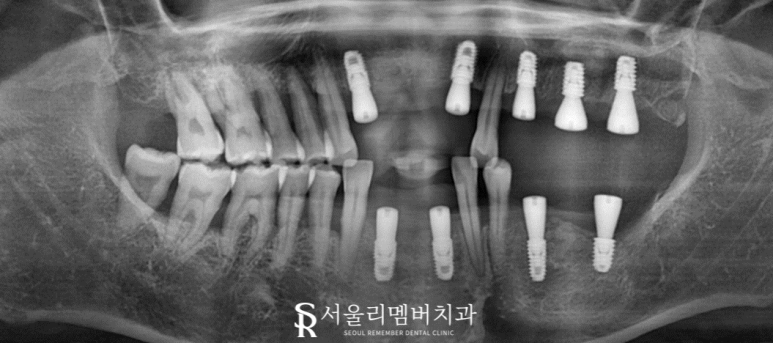

자, 본격적으로 계획을 세우기 위해 엑스레이 촬영을 진행했습니다.

그 결과 구강 내에서는 발견하지 못했던 부분들도 함께 관찰되었는데요.

왼쪽 어금니와 앞니에서 뿌리 부근 염증이 발견되었으며 치아가 위, 아래로 움직이는 정출까지 나타났습니다.

치조골 상태를 보면 치아를 지지할 수 없을 정도로 소실이 심해 보였는데요.

자연 발치가 이뤄져도 이상하지 않을 정도라면 이해가 쉬우실까요..?